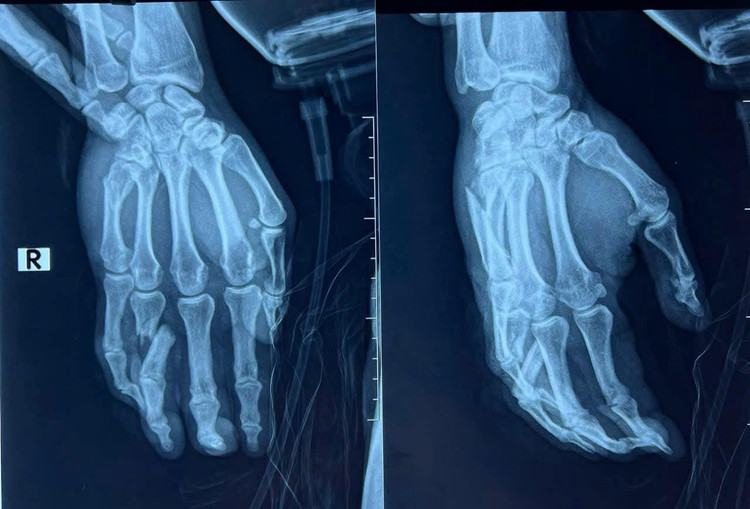

| Hình ảnh tổn thương xương bàn tay và ngón tay - Ảnh BVCC |

Ngày hôm qua 22/01/2025, anh S đã được tiến hành mổ nẹp xương bàn tay và ngón tay phải.